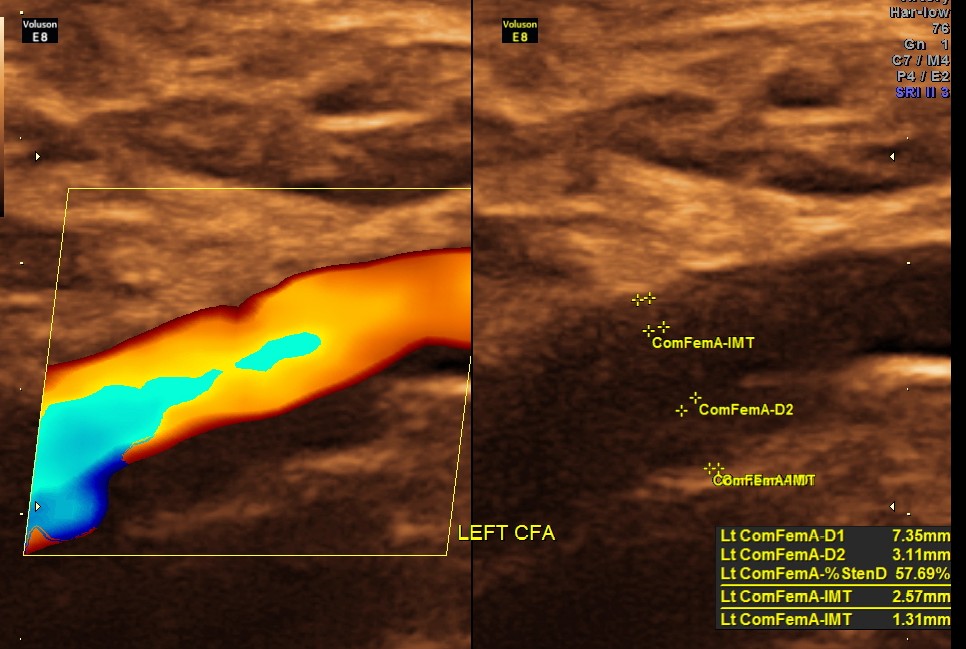

Rt Common Femoral artery showed nearly 70 % obstruction.

EXTENSIVE ATHEROSCLEROTIC OBSTRUCTIVE DISEASE OF THE LOWER LIMB ARTERIES WAS SEEN WITH THE CHANGES IN THE RIGHT COMMON FEMORAL ARTERY BEING MORE THAN THE LEFT CFA.